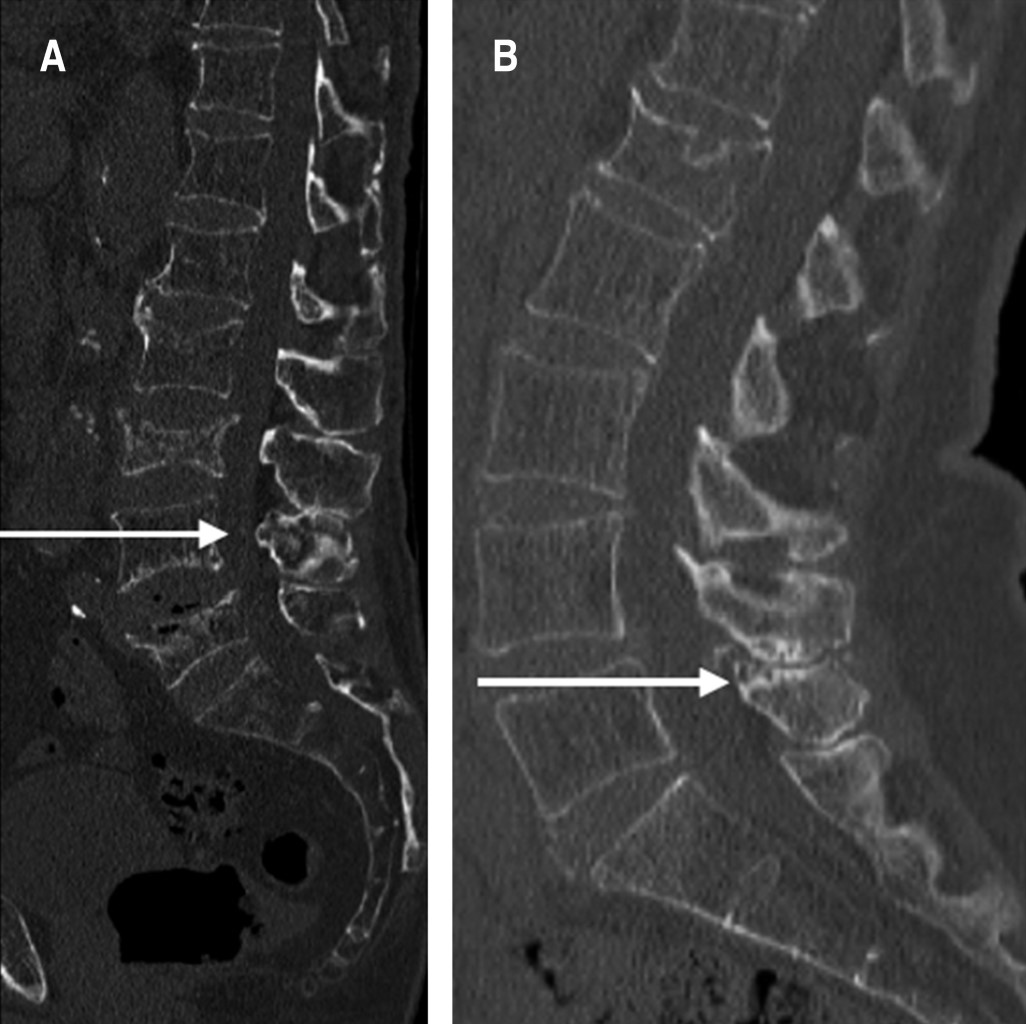

Introduction: low back pain is a frequent reason for consultation, its prevalence increases with age, it is estimated that 60 to 90% of the adult population will develop low back pain throughout their lives, becoming one of the main reasons for absenteeism. work in Mexico. Baastrup disease is a little-known cause of low back pain; it is caused by abnormal contact between the lumbar spinous processes during flexion-extension movements. It is attributed as one of the main causes of chronic low back pain as part of the degenerative process of the spine; however, due to the lack of diagnostic suspicion, directed treatment is rarely indicated, which triggers persistence of symptoms and therapeutic failure. Objective: to establish the prevalence of Baastrup disease in patients over 60 years of age with chronic low back pain and determine the findings in imaging studies, with the aim of increasing the diagnostic suspicion of said condition and including it in the list of possible causes of low back pain. at the Social Security Institute of the State of Mexico and Municipalities (ISSEMyM). Material and methods: cross-sectional and descriptive study, in which a total of 504 patients over 60 years of age with a diagnosis of chronic low back pain who underwent lumbar spine imaging studies were included. Results: the imaging studies of 504 patients were analyzed, of which in 267 cases (97 men and 170 women) changes compatible with Baastrup disease were found, thus establishing a prevalence of 52.97% in the studied population; however, in none of the cases mention this condition as a diagnostic conclusion. In all cases, a decrease in the interspinous space, reactive sclerosis and flattening of the interspinous contact surfaces were observed. Conclusions: Baastrup disease has a high prevalence in patients over 60 years of age with chronic low back pain. In advanced stages the diagnosis can be established through radiographic studies of the lumbar spine.REFERENCES